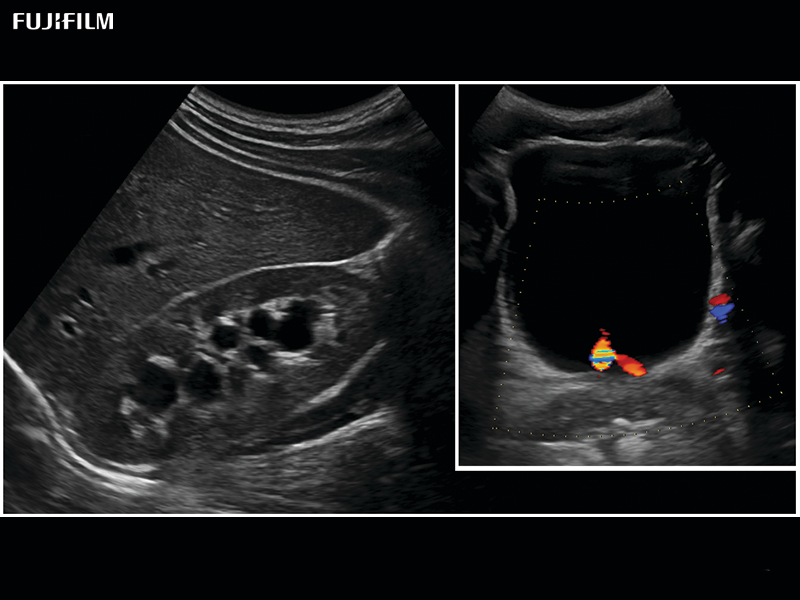

Linear transducer that is ideal for scrotal and penile doppler imaging. Trapezoid Display extends field of view and enables visualization of entire structure.